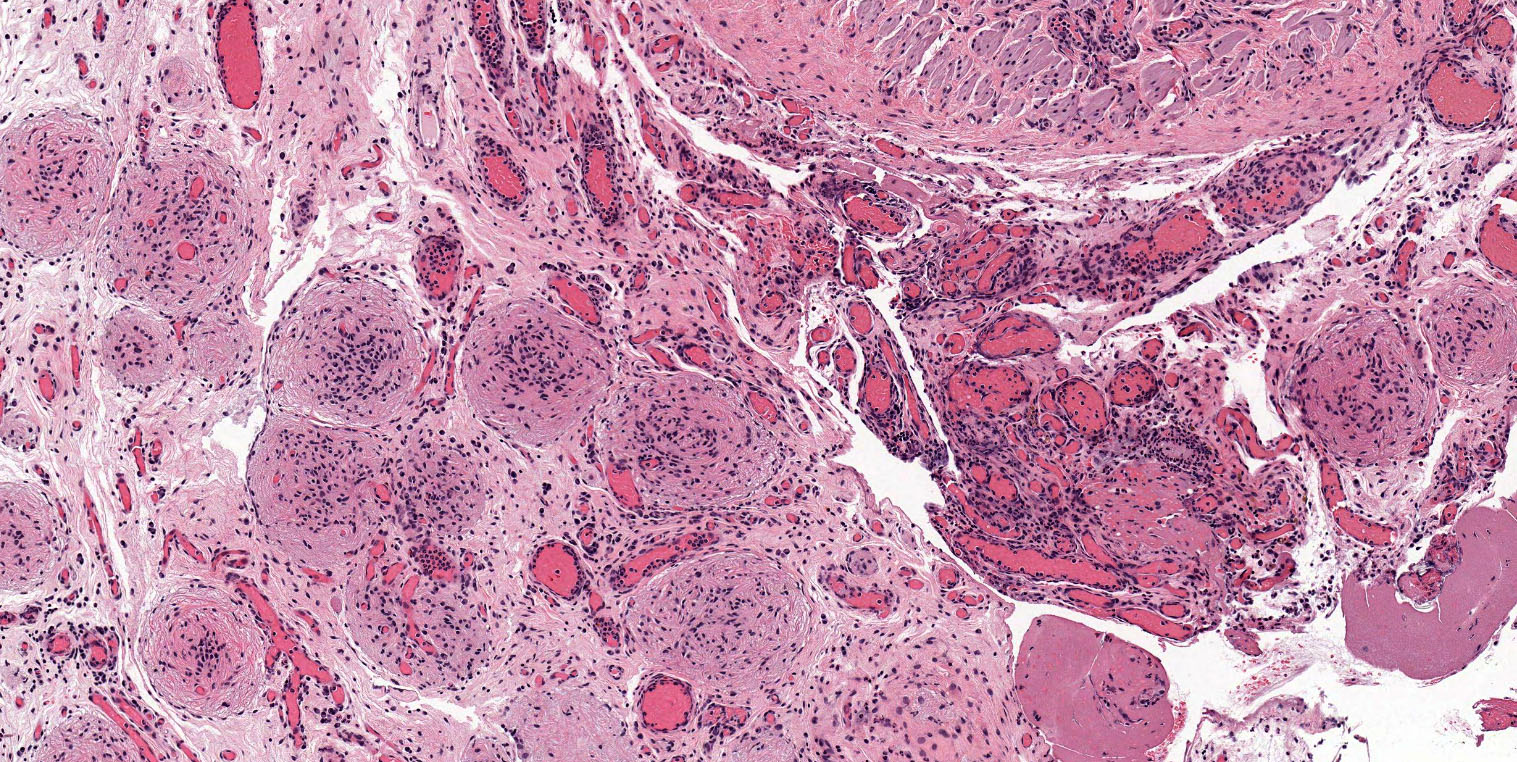

Microscopic (histologic) description

- Mixture of mature, benign tissues

- Ectodermal (most common): squamous epithelium, sebaceous glands, hair follicles, brain tissue

- Mesodermal (second most common): bone, cartilage, smooth muscle, fibroadipose tissue

- Endodermal: intestinal or respiratory epithelium, thyroid, salivary gland

- Fat necrosis and foreign body reaction may be seen

Microscopic (histologic) images